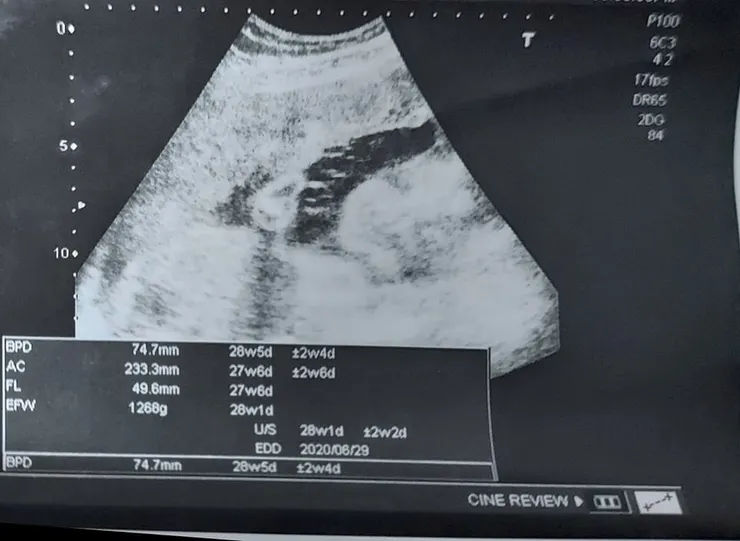

2020.4.09(二) (2020.4.7--28W5D--1266G)

周二前常常覺得寶寶有種要掉出來的感覺,因為常常覺得寶寶在肚臍以下,然後走路都會不舒服,晚上睡覺也會覺得,不知道是寶寶的哪裡突然換位置,讓我的肚臍下方鼓起來,扯到我的肉,沒想到產檢的時候,醫生的確說寶寶有點太下面,他是頭朝下趴著,他也太早朝下了吧,是和我一樣等不及出門了嗎??聽完醫生雖然說再觀察,他可能會換位置,我都覺得醫生好安慰人喔,而且還說要我多躺著,坐也沒用,能躺著就躺著,好在我辭職了,真的可以爽爽躺,證明辭職是對的!

而且的確因為他游上來,所以胎動比較上面,不然之前他在肚臍以下動,很容易踢到我,覺得膀胱酸酸想尿尿,另外醫生說他現在大了兩周,目前體重1280克,也請大家為我祈禱吧!!希望不要生到太大的寶寶,雖然我和天主說我願意,但是我對生小孩還是持續有恐懼,這種東西就是答應不能回頭的不可逆阿!!